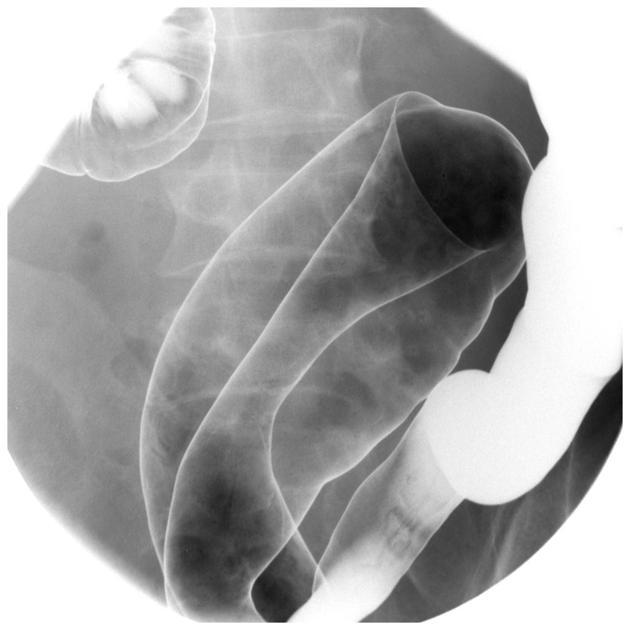

Barium enema of “lead pipe colon”

Loss of haustral marking characteristic of UC

Apple core colon

Characteristic of colorectal carcinoma